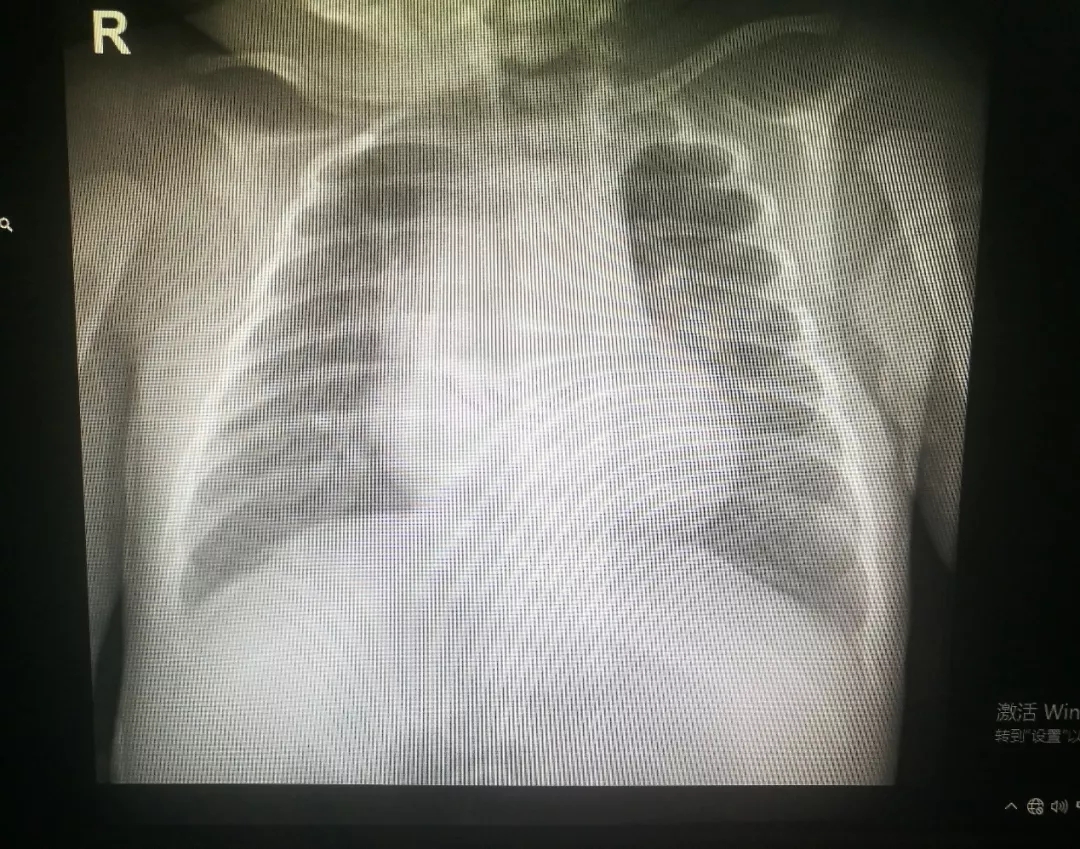

术后胸片

在新生儿科医护团队的悉心治疗及护理下,患儿病情稳定,逐渐予撤除有创呼吸机改为经鼻高流量给氧支持治疗,复查胸片提示右肺不张明显好转,治疗效果显著。现患儿处于康复阶段。该患儿成功实行电子支气管镜灌洗治疗,标志着我院新生儿支气管镜诊疗技术又上了一个新的台阶。